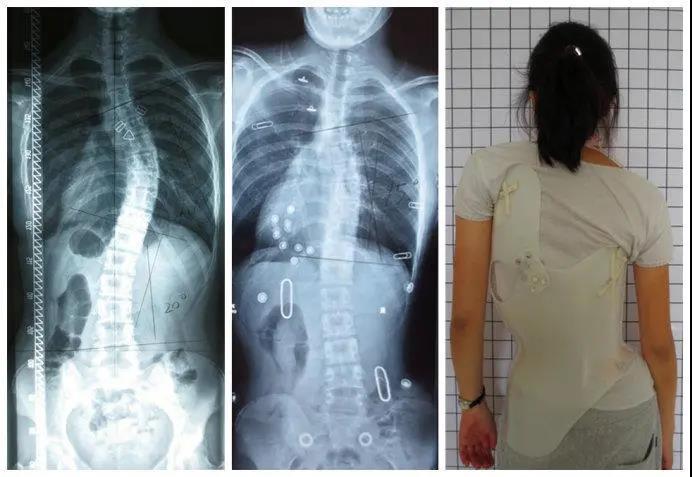

脊柱侧弯是脊柱的三维畸形,冠状面侧方弯曲,水平面轴向旋转,矢状面生理弯曲,前凸或后凸异常。而超过80%的脊柱侧弯是原因不明的,好发于青少年特发性脊柱侧弯,其中又以女性最为多见。

(脊柱矢状面上胸椎后凸,冠状面上S型弯曲,腰椎前凸曲度减少,椎体和骨盆旋转)QUESTION-02

目前国际上公认的方法就是手术治疗和保守治疗,通常根据患者的年龄、性别、剩余生长潜力、躯干旋转角度及Cobb角(脊柱侧弯严重程度的参考标准之一)的大小等因素来选择合适的治疗方案。